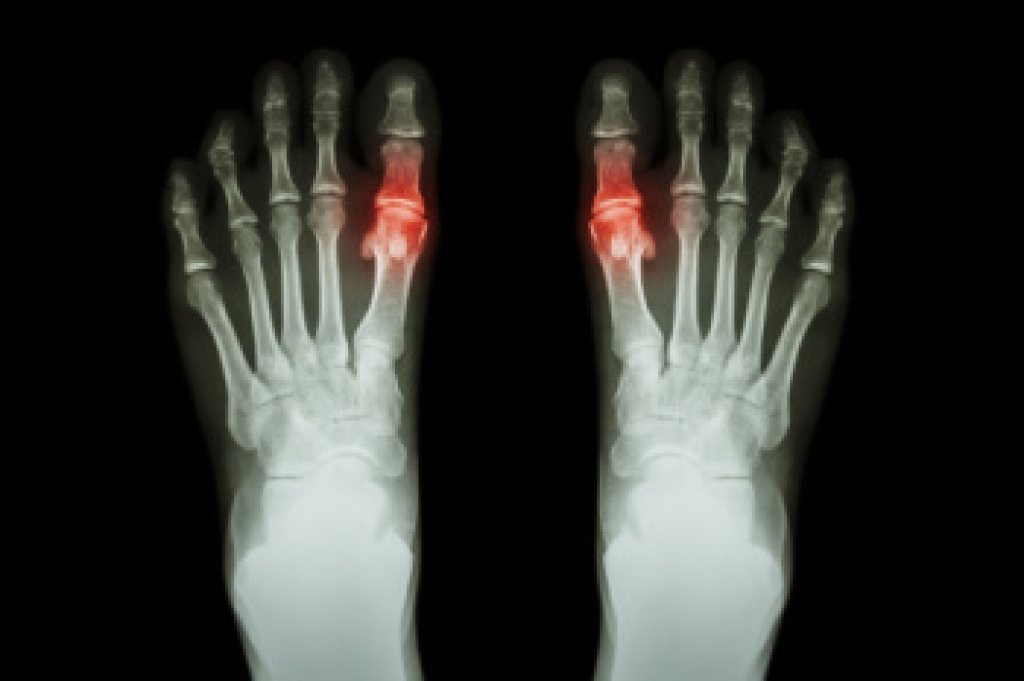

While it may not seem apparent with small ulcers on the foot, for diabetics, any size ulcer can become infected. Diabetics often also suffer from neuropathy, or nerve loss. This means they might not even feel when they have an ulcer on their foot. If the wound becomes severely infected, amputation may be necessary. Therefore, it is of the upmost importance to properly care for any and all foot wounds.